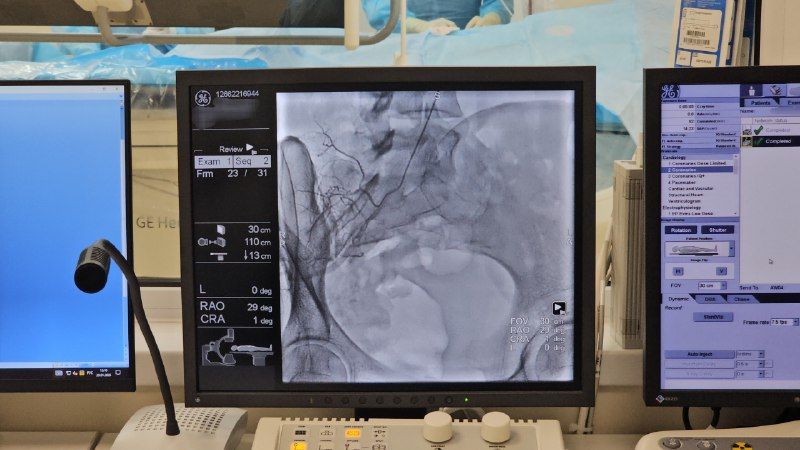

Региональный сосудистый центр Центральной городской больницы Бийска более года успешно оказывает высокотехнологичную помощь пациентам с сосудистыми патологиями.За этот период центр принял свыше 1 700 пациентов и...